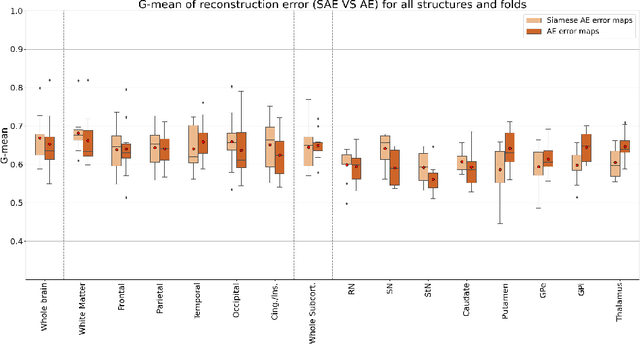

Although neural networks have proven very successful in a number of medical image analysis applications, their use remains difficult when targeting subtle tasks such as the identification of barely visible brain lesions, especially given the lack of annotated datasets. Good candidate approaches are patch-based unsupervised pipelines which have both the advantage to increase the number of input data and to capture local and fine anomaly patterns distributed in the image, while potential inconveniences are the loss of global structural information. We illustrate this trade-off on Parkinson's disease (PD) anomaly detection comparing the performance of two anomaly detection models based on a spatial auto-encoder (AE) and an adaptation of a patch-fed siamese auto-encoder (SAE). On average, the SAE model performs better, showing that patches may indeed be advantageous.